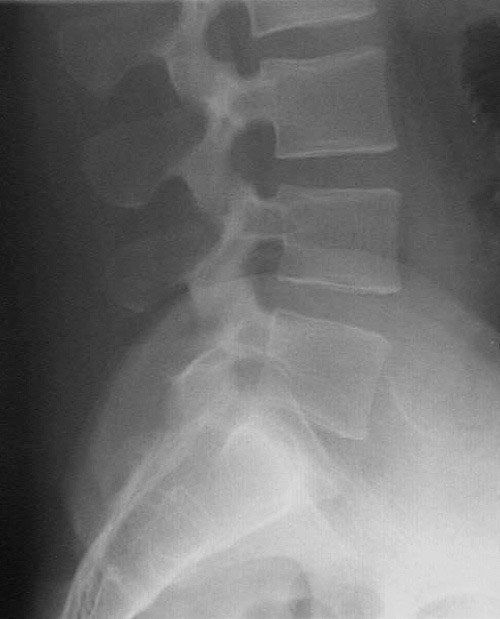

This is a normal lateral radiograph of the lumbar spine demonstrating the L3 vertebral body and pedicle and spinous process and intervertebral disc and apophyseal joint and iliac crest and sacrum.